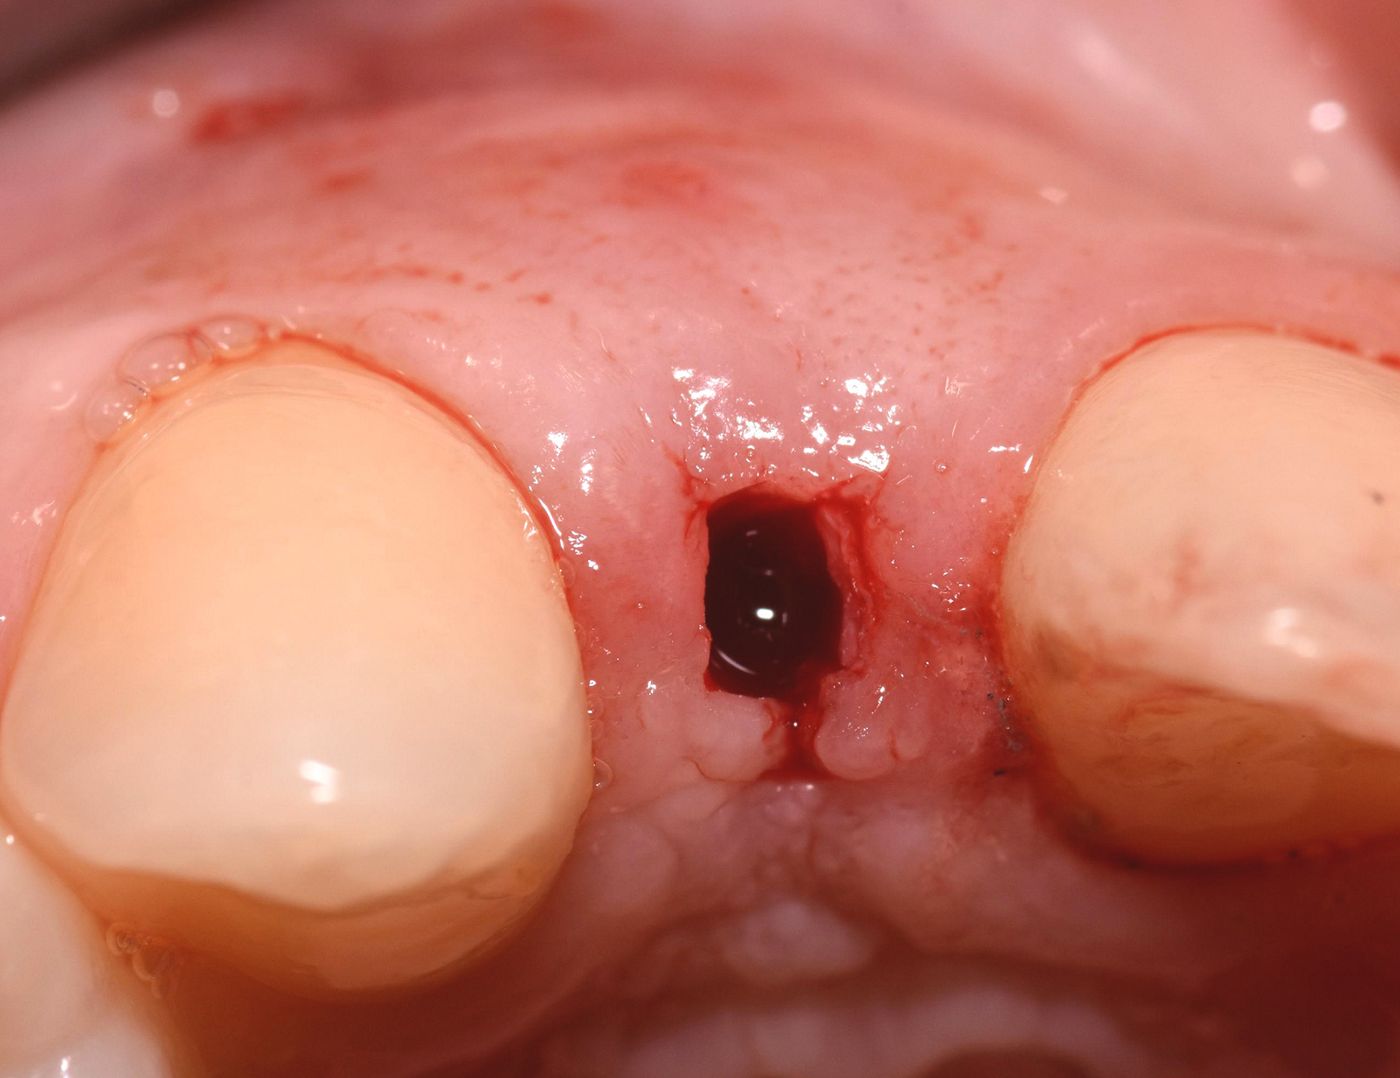

Some 4 months after surgery, a minimal access incision to the implant was made. (Fig. 22)